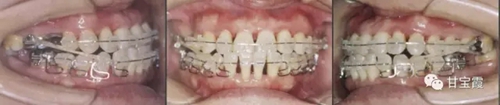

上圖為矯正中的咬合像